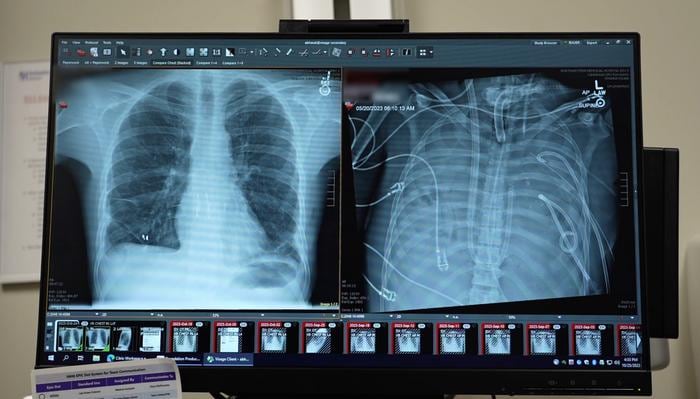

Durante 48 horas, el paciente permaneció sin pulmones, con el tórax vacío y conectado únicamente al sistema artificial. El equipo médico vigiló de cerca su evolución y, al confirmarse la mejoría, logró ingresar al paciente en la lista de trasplantes. Dos días después, se realizó el trasplante doble de pulmón. Más de dos años después del procedimiento, el paciente mantiene una vida normal y sus pulmones funcionan correctamente.